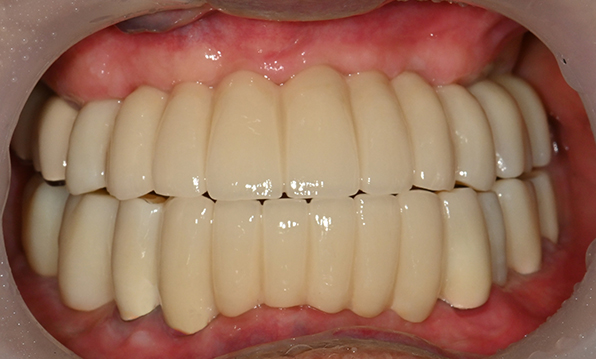

전체 임플란트

위 아래 치아가 정확하게 맞아야하는 고난이도 임플란트

임상 경험이 많은 숙련된 전문의의 섬세한 기술력이 중요합니다.

치료기간 : 2021.04.12~2021.09.15